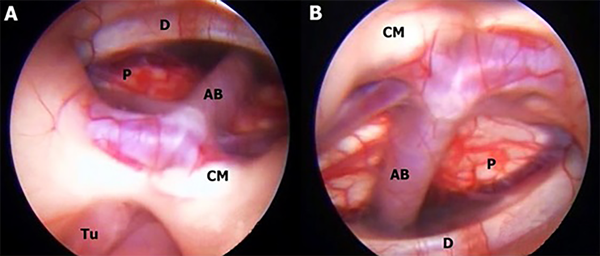

En este estudio fueron halladas 10 variedades anatómicas del piso anterior del tercer ventrículo, las cuales son en orden de frecuencia: piso opaco o grueso 54,90% (Figura 1), piso parcialmente borrado 29,41% (Figura 2), intervalo prepontino pequeño 23,53% (Figura 3), piso estrecho 17,65% (Figura 4 A-B), piso herniado 17,65% (Figura 5), piso delgado 11,76% (Figura 6), basilar elevando el piso 1,96% (Figura 4C-D), adherencias interhipotalámicas 3,92% (Figura 7), fenestración espontánea 1,96% (Figura 8), y piso sin reparos anatómicos 1,96% (Figura 9). Las primeras 7 según la descripción de Sughrue, a la cual se sustituye banda premamilar por adherencias interhipotalámicas, descriptas por Phillips4, fenestración espontánea al hallarse ausencia de PTV u ostomía espontánea como en la Fig. 8, reportada por Parmar5, y se introduce otra categoría no reportada, piso sin reparos anatómicos cuando no se pueden diferenciar los cuerpos mamilares ni el receso infundibular. En la mayoría de los casos se detectaron 2 o más variedades.

Figura 8: A-B: Mujer de 34 años con tumor a nivel de región pineal, hidrocefálica, presentándose con síndrome de Parinaud, por lo que se decide realizar TVE más biopsia, observándose en el intraoperatorio fenestración espontánea del PTV con ausencia total de Membrana de Liliequiest. AB arteria basilar; CM cuerpo mamilar; D dorso selar; P puente; Tu tumor.

Figura 9: A-B: Mujer de 55 años con tumor a nivel de hemisferio cerebeloso izquierdo y otro en región selar. No se identifican landmarks. Presencia de placas blanquecinas en la pared anterior del tercer ventrículo. No se puede realizar TVE y se deja DVE.

Un evento raro es la ventriculostomía espontánea. Se ha informado en varios lugares, incluido el atrio del ventrículo lateral, el receso suprapineal y el PTV. Ocurre en el contexto de una hidrocefalia crónica, cuando la pulsación crónica del LCR a alta presión actúa contra regiones delgadas de la pared ventricular y da como resultado la penetración transmural y la ruptura de la pared ependimaria hacia el espacio subaracnoideo. Esto a menudo conduce a una resolución de los síntomas de hidrocefalia.5 Nosotros reportamos un caso (Figura 8) en una paciente con un tumor de región pineal.

Por último, en nuestra revisión hemos encontrado un caso (Figura 9) donde fue imposible la correcta identificación intraoperatoria de los landmarks usuales del PTV - el receso infundibular y los cuerpos mamilares, debiendo suspender la TVE.